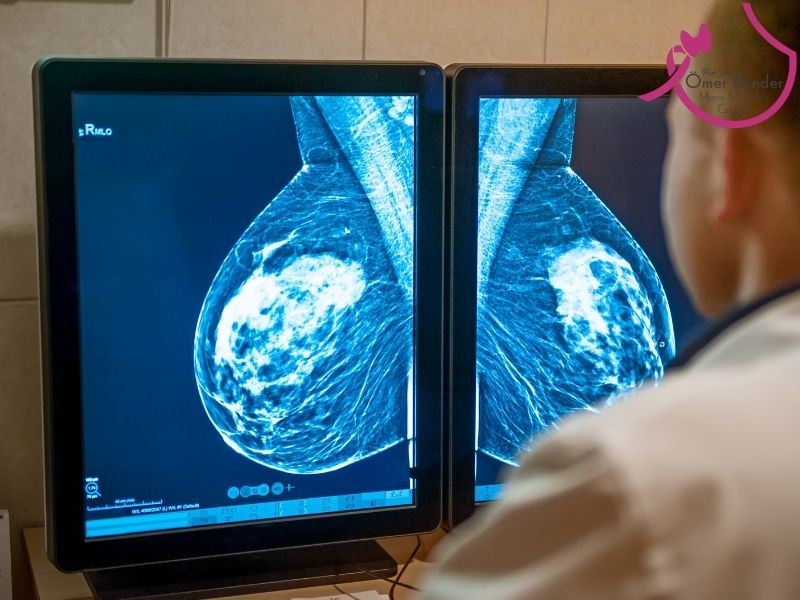

Meme kanserinin evrelenmesi, kanserin ne kadar yayıldığını ve ilerlediğini değerlendiren bir süreçtir. Meme kanserinin tedavisi, hastalığın içinde bulunduğu evreye (stage) göre planlanır. Evreleme için 3 temel faktör göz önüne alınır:

- Tümörün boyutu

- Lenf düğümlerine atlayıp atlamaması

- Diğer organlara atlayıp atlamamış olması